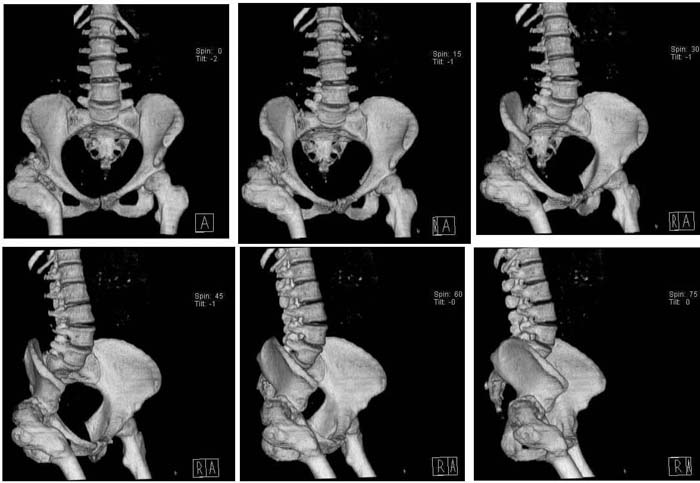

Уважаемые коллеги!Женщина, 35 летВ прошлом по поводу врожденного вывиха бедра перенесла операцию остеотомии по Шанцу

с удлинением правой ноги за счет бедра на уровне диафиза. В последнее время прогрессируют боли в правом тазобедренном суставе, порочное положение правой ноги, затруднена ходьба.Вопросы:1) Целесообразно ли эндопротезирование правого тазобедренного сустава?2) Целесообразный ли следующие действия: канал бедренной кости предполагаем вскрыть для введения ножки протеза на высоте угловой деформации, предполагаем низведение большого вертела с мышцами; протез будет подобран индивидуально, предполагается умеренная версия?В приложении рентгенограммы и трехмерная КТ.В цветном и более качественном варианте КТ размещена здесь

123456